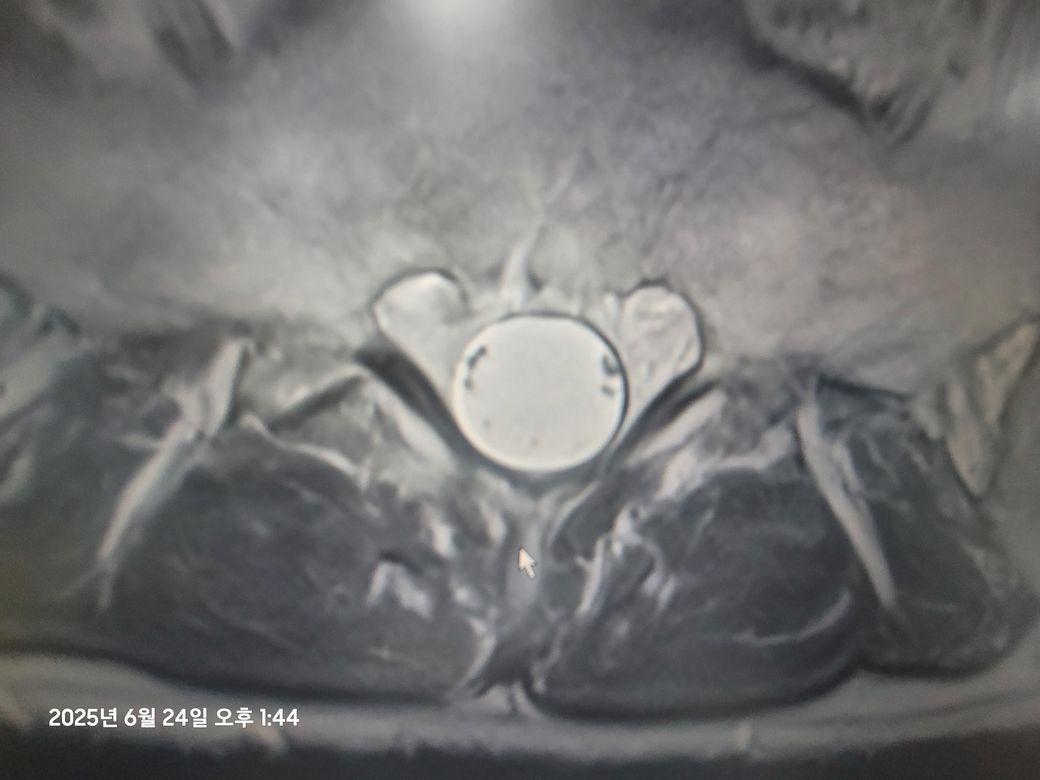

• 2번 째 사진